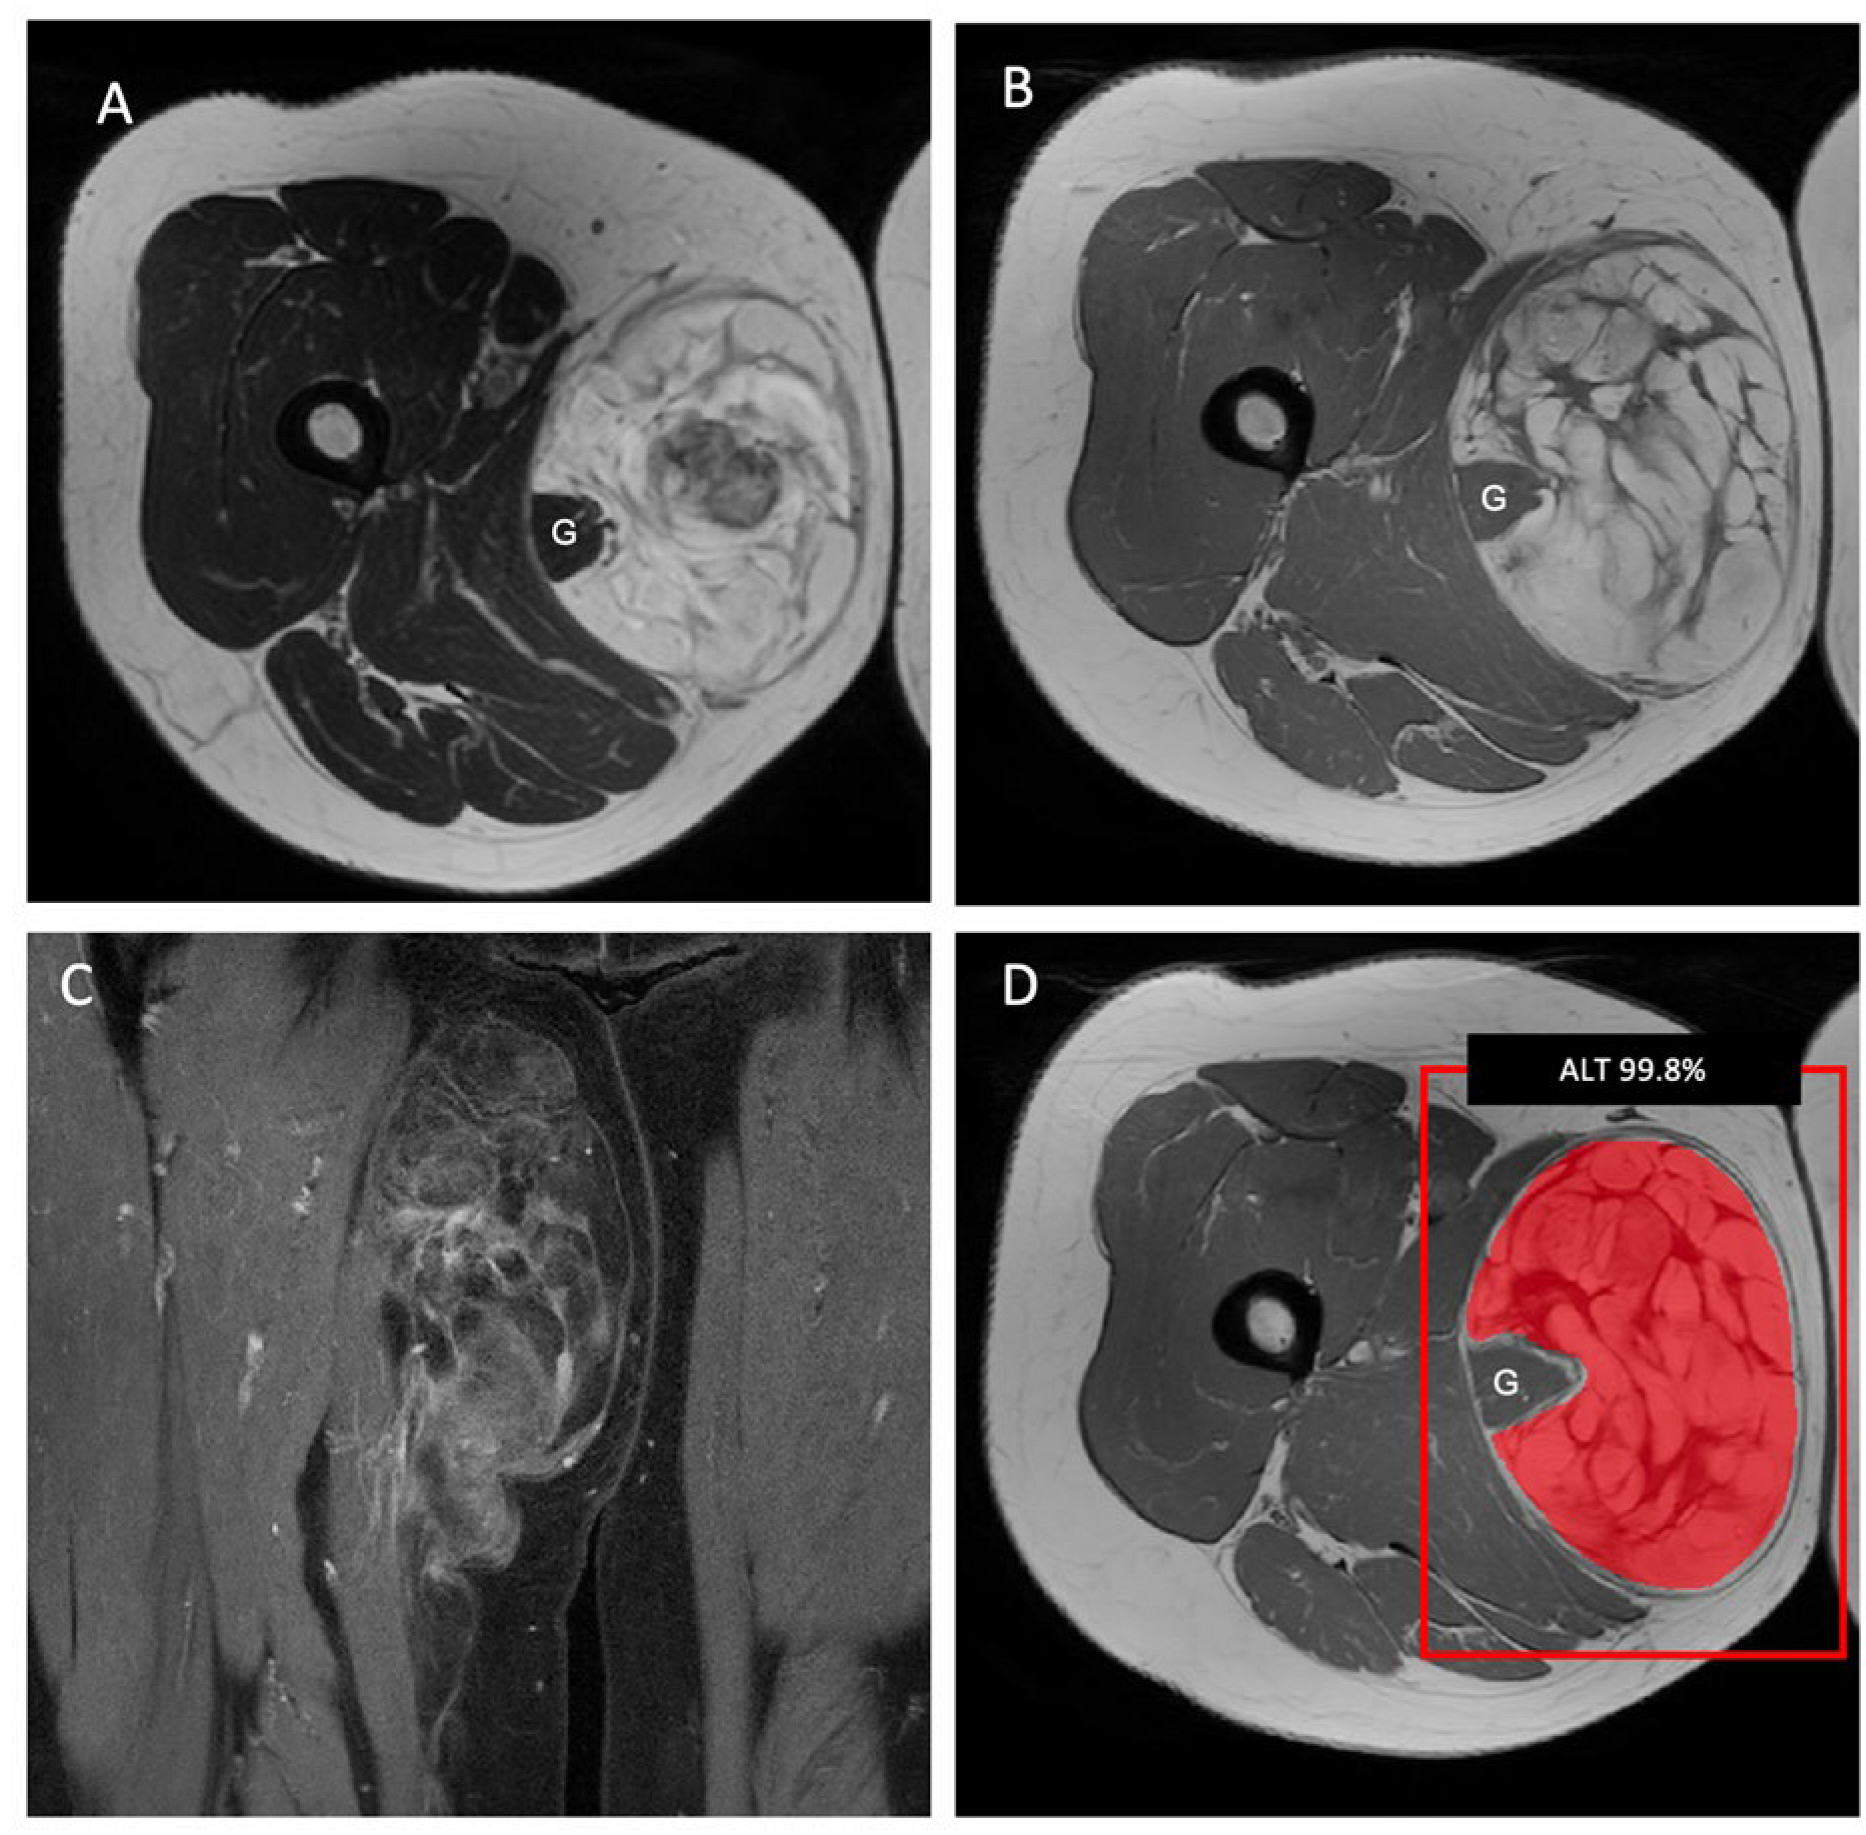

2.2. MR Imaging Protocol and Image Segmentation

2.3. Radiomic Feature Extraction and Machine-Learning Model Development